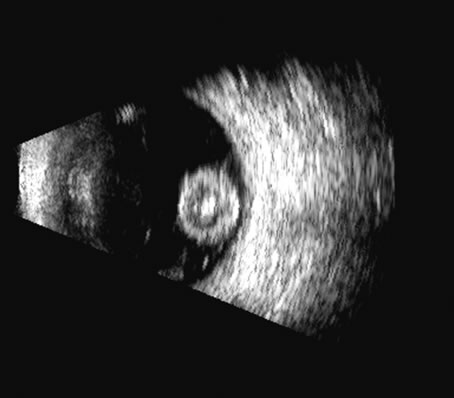

Fig. 14. A B-scan of an eye with “kissing” choroidal detachments. The smooth convex outline from the ciliary body back to the near periphery of the posterior pole can be seen. The choroidal space, though filled with blood, may often appear anechoic due to the recent, “fresh” nature of the hemorrhage.